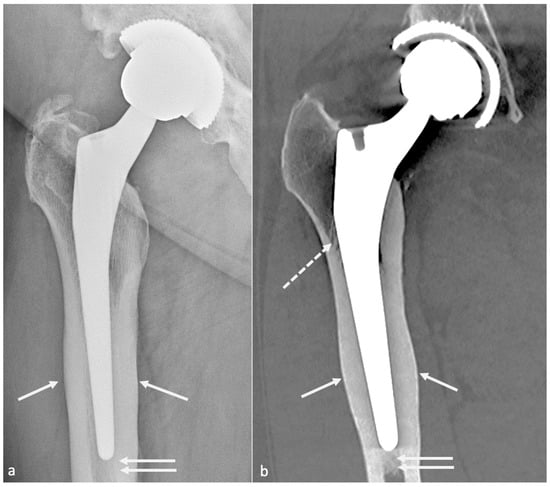

4.3.3. Radiographs, Tomosynthesis, and CT

- Gillet, R.; Teixeira, P.; Bonarelli, C.; Coudane, H.; Sirveaux, F.; Louis, M.; Blum, A. Comparison of Radiographs, Tomosynthesis and CT with Metal Artifact Reduction for the Detection of Hip Prosthetic Loosening. Eur. Radiol. 2019, 29, 1258–1266. [Google Scholar] [CrossRef]